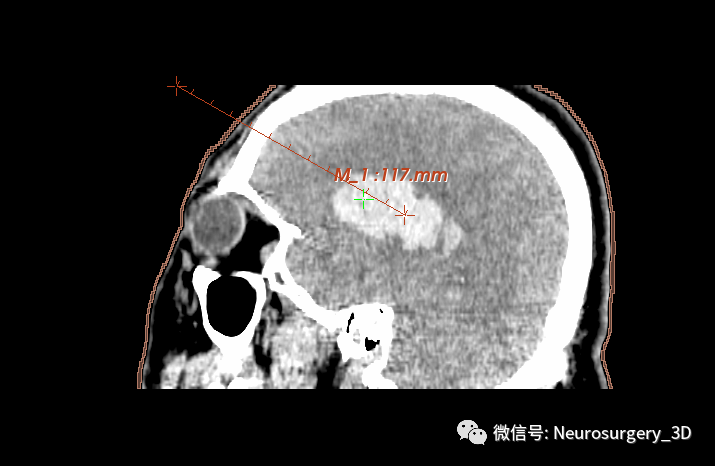

1、利用Ruler测量出穿刺血肿靶点至穿刺外口的距离,并设计出穿刺路径顺血肿长轴走形在血肿中心(并非如下图所示所有穿刺路径均与矢状面平行、请注意穿刺深度),避开颅内重要结构如额窦、上矢状窦等。

入颅点避开了额窦、上矢状窦

透视化血肿状态下显示穿刺路径走形在血肿中心